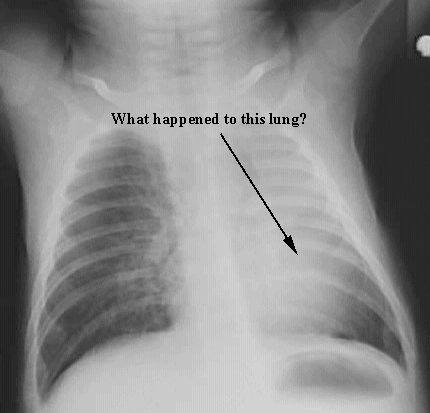

Thorax- Collapsed lung Child

Arrows: Lung details disappeared. No air.